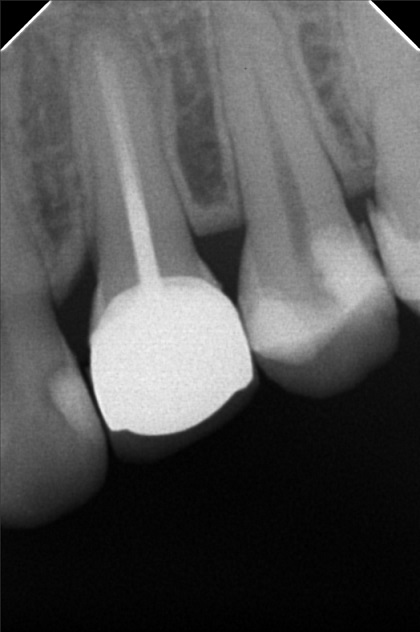

Edit Record Check our patient data records. Add patient information Patient Info Profile picture Last Name First Name Middle Name Birthdate Age Street Barangay City Country Zip Code Contact number Email Procedure 10/13/21- 26 LC with MTA MOD 23 Lingual Distal 11/24/21 - 25/27 LC# 27 #15 IRM -/Xray 03/16/22- zircinia prep on 15/16 shade: a3 body, cervical b3 digital impression done temporary crown done LC mesial 15, distal 14 xray on 24 3/25/22- installation 15, 16 zirconia opening of canal 24 TF with EUgenol 03/30/22 Lingual 18/ Buccal 19 Formocresol Incision and drainage Laser rx: co amoxiclav 625 mg/ mefenamic 500 mg 04/29/22- lingual 16.5mm buccal 19mm 05/04/22- obturation/ LC 8/12/22 - tooth prep #24 8/18/22- Cementation zirconia crown #24 8/26/22 - xray, intraoral radiograph 05/12/23- OP(L) 05/19/23- Xray/ Ozone/Resto - #21(mesial & lingual) 09/10/24 OP w/ air polisher 07/19/25 op with air polisher + fluoride 03/18/26 OP 04/08/26 #48 - Occ mesial MTA Fiber Biomimetic File delprado26.jpg File 2 delprado23-24-25.jpg File 3 6afb059c-2de8-4dc8-ac4d-ae6435b6dabc.jpeg File 4 katherine_del_prado.jpg File 5 katherine_del_prado_02.jpg File 6 katherine_del_prado_03.jpg File 7 File 8 File 9 File 10 File 11 File 12 File 13 File 14 File 15 File 16 File 17 File 18 File 19 File 20 Retain Record Retain Record Yes No Save Your Changes